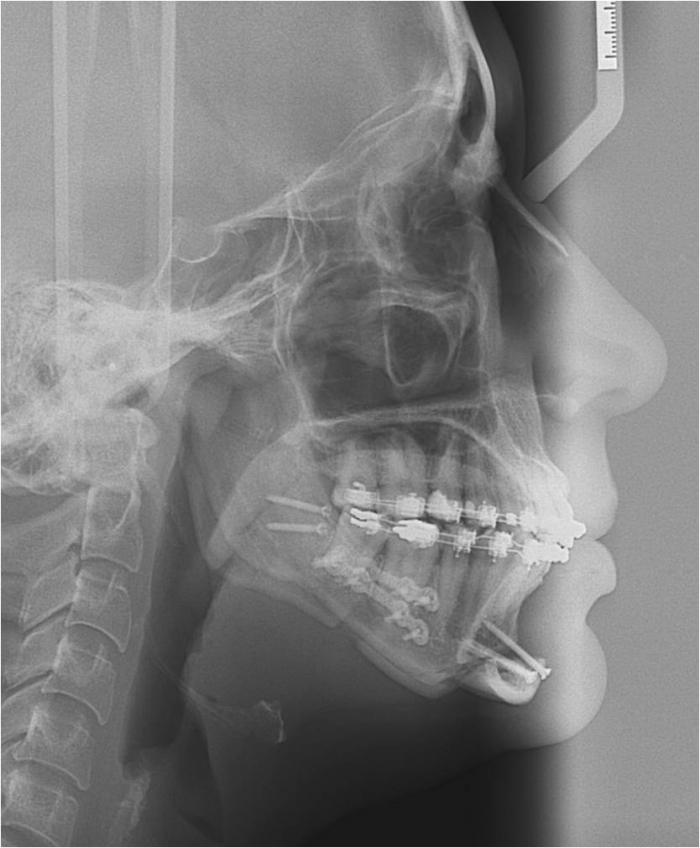

Telerradiografia final